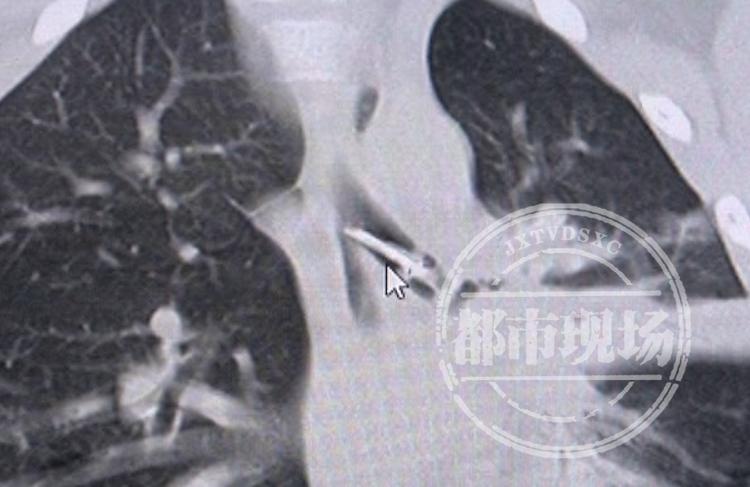

江西省儿童医院耳鼻咽喉科主治医师 熊晶晶:胸部CT提示,图钉在左侧主气道里面,图钉的直径跟10岁左右孩子的主气道的直径相接近,一旦顶到了声门,卡在声门不动,随时有出现窒息死亡的可能。